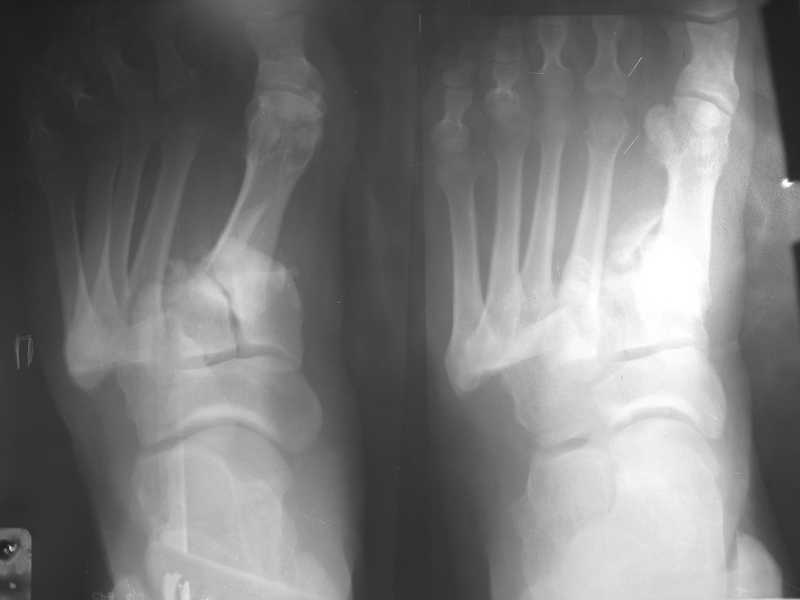

Здравствуйте , уважаемые коллеги. Обратился пациент, мужчина 42лет. для дальнейшего

лечения. Травма 11.09., ДТП.

15.09 проведено оперативное лечение (Блокирующий стержень левого

бедра - статическая система. Открытое вправление вывиха в суставе

Лисфранка и фиксация мет. фиксаторами.)

D.S. Переломы диафиза и межмыщелковой области левого бедра, вывих в

суставе Лисфранка правой стопы. Состояние после МОС. Через 6 нед.

контрольная Ro, (снимки прилагаются).